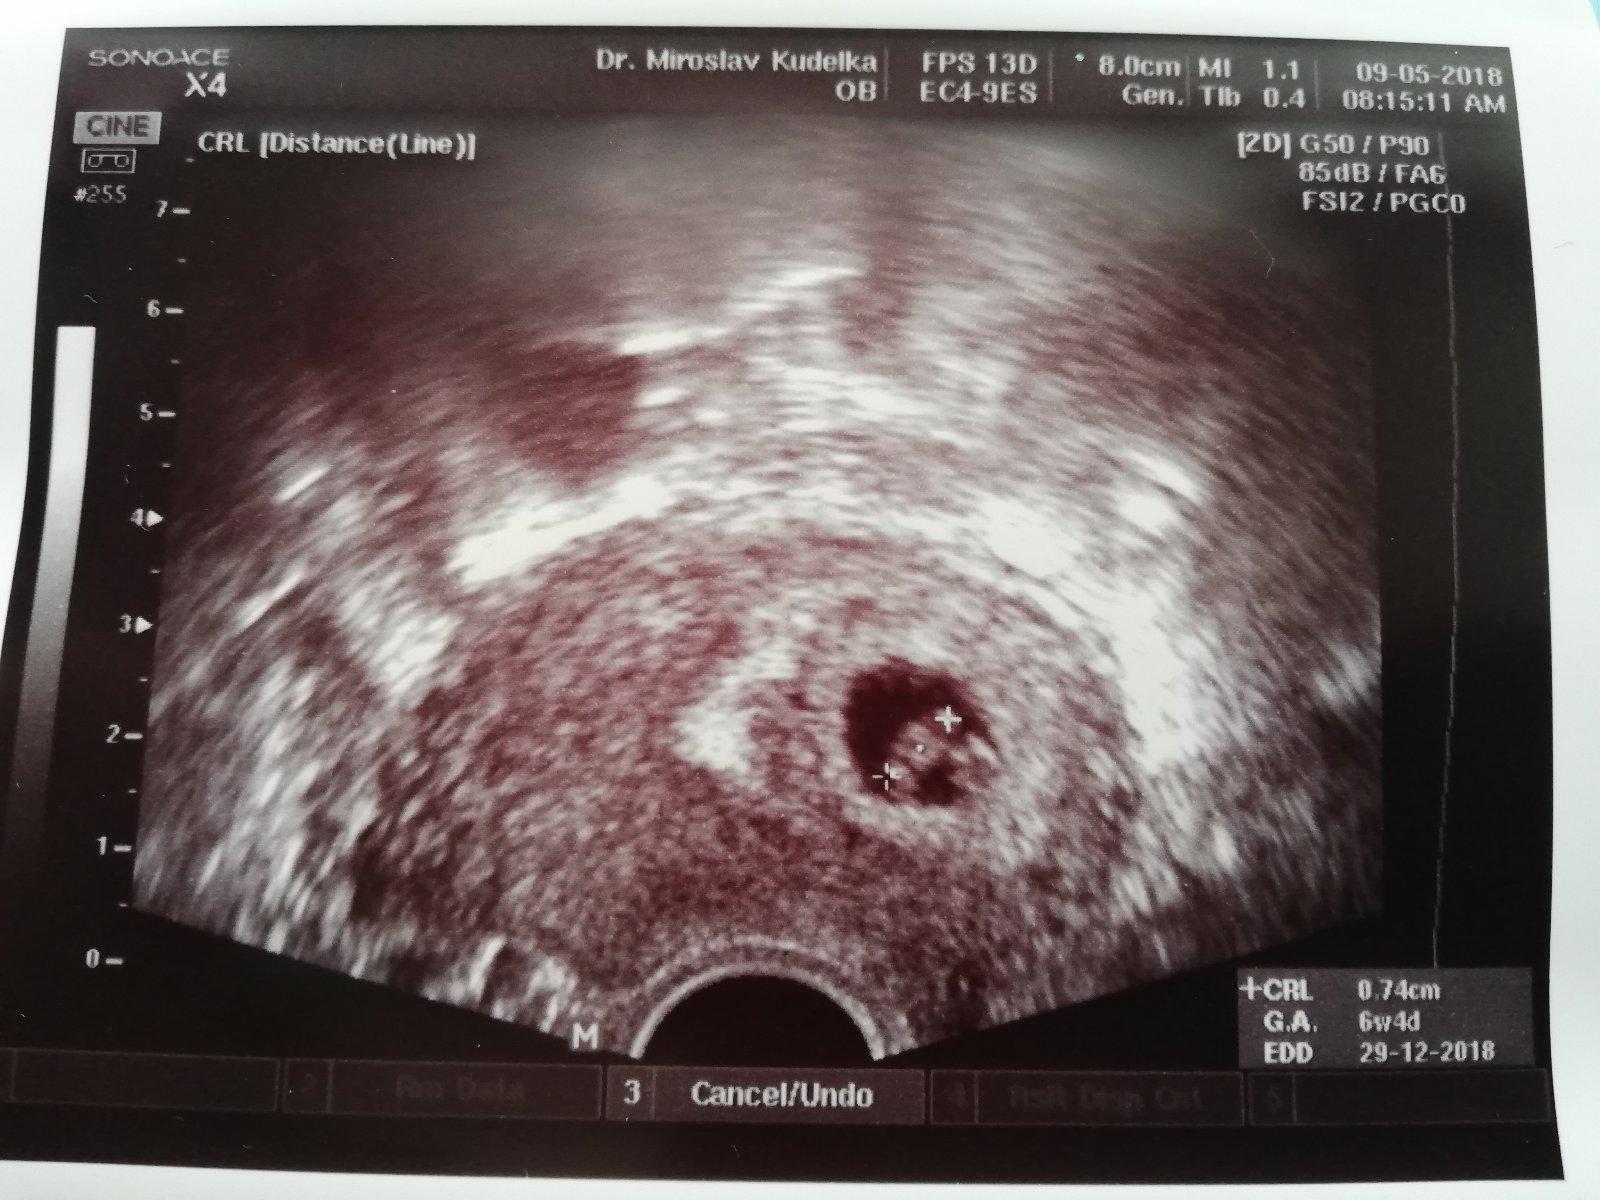

Srdíčko našeho druhého drobečka krásně bije a vše je v naprostém pořádku, dle ultrazvuku jsem 6+4tt a dle ms jsem 6+5tt 😊 😍 Při pohledu na tlukouci srdíčko jsem se rozbrečela🤗

Termín porodu dle UTZ 29.12. 😁